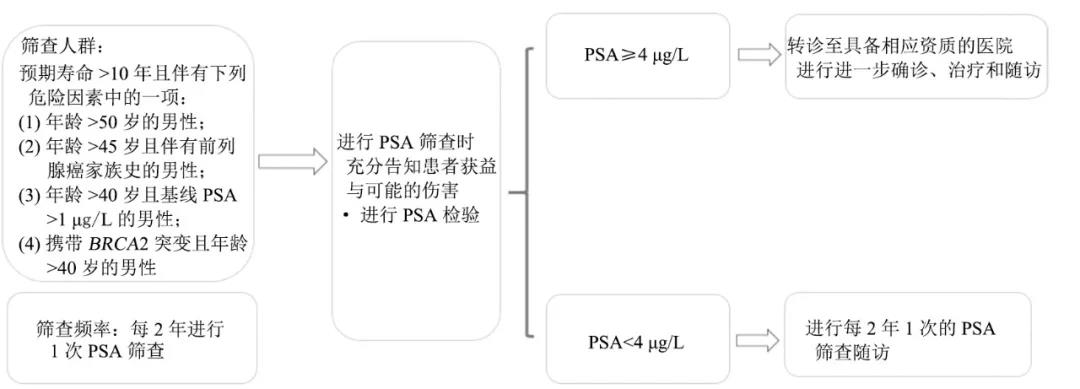

1 前列腺癌流行病学特征随着中国经济水平提高、人民生活水平改善和人均寿命延长,中国前列腺癌的发病率呈显著上升趋势,正逐步成为影响中国中老年男性健康的重要疾病[1]...